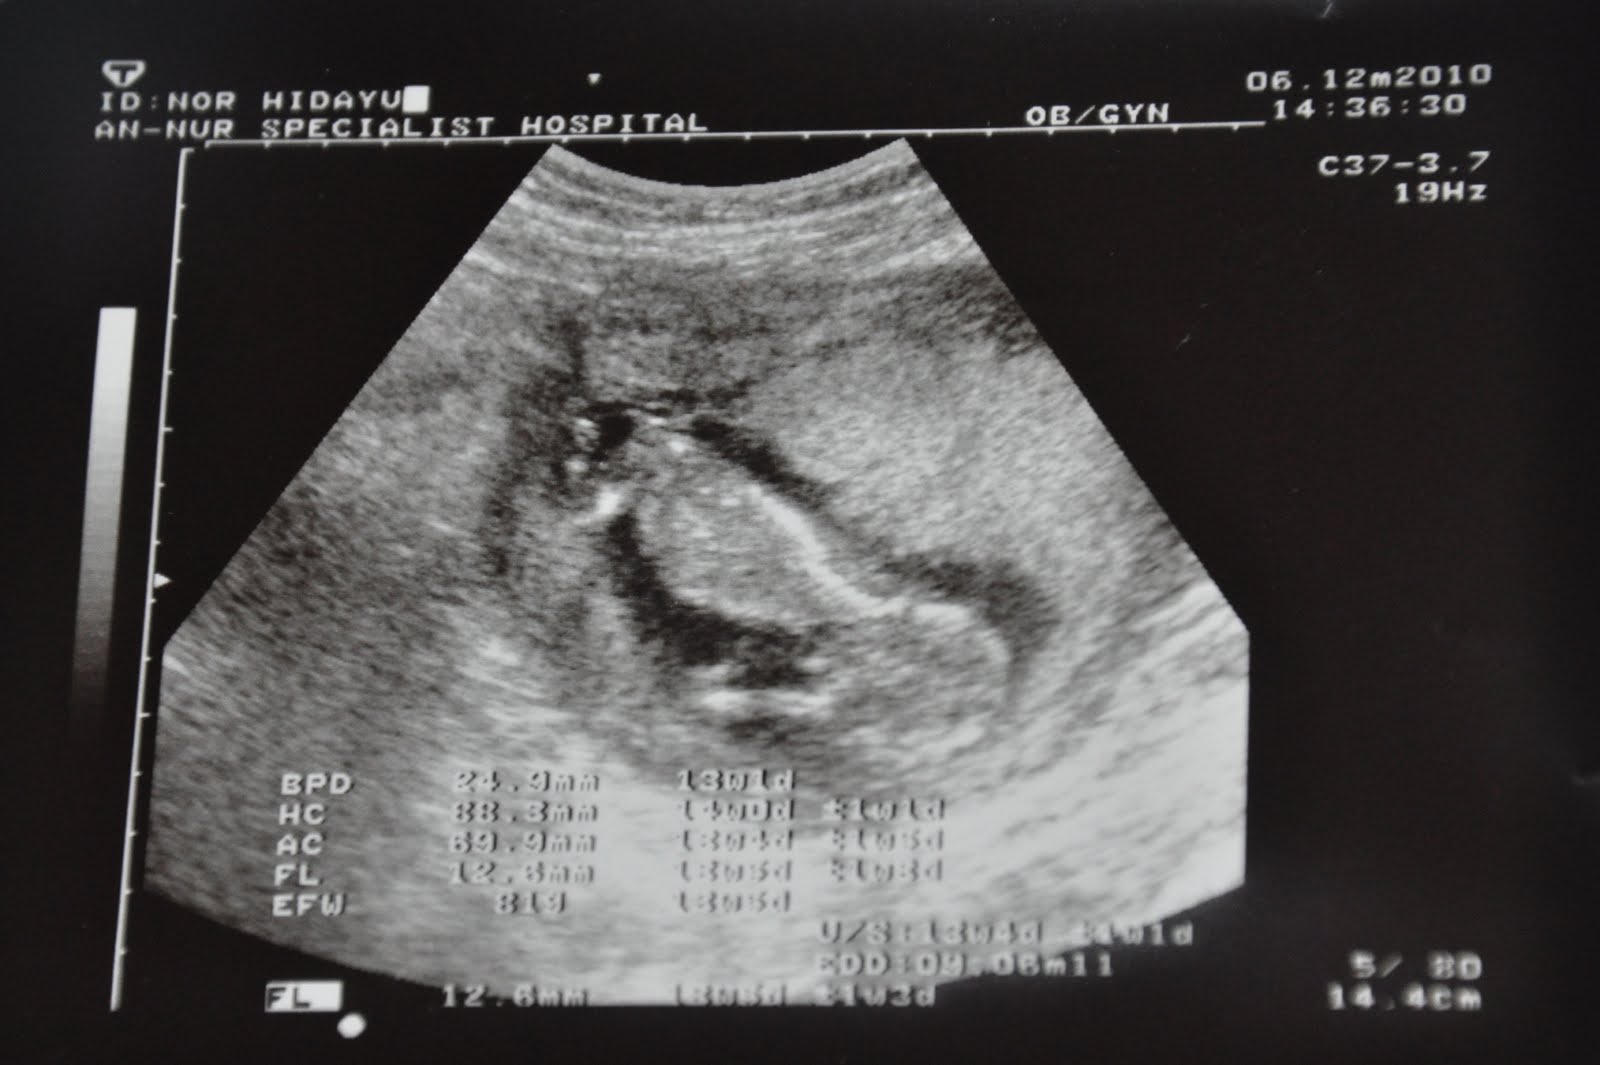

Ni la pic scanning baby mase hari isnin tu.. first time tengok ni...hehehe... seronok je die berenang2... mase g check up tu, kandungan dah 16 minggu kalo ikut kiraan last period... tapi doc Kham cakap, kalo ikut scan sebenarnya baby baru berusia 13 minggu... hmmm... mugkin sebab period aku x btul..dah lari pulak due date .. sepatutnya 22 Mei 2011.. kat scan dh jadik 08 Jun 2011... ermmmm... x kisah la.. janji anak ibu ni selamat, sihat, dan sempurna semasa dilahirkan nanti ye... Insyaallah... semoga Allah perkenankan doa ibu... tak sabar menanti kelahiranmu ke dunia...

ni la pic penuh baby... jelas nampak kepala, badan, tangan, kaki, tali pusat ngan uri... jom zoom lagi skit bagi jelas..=)